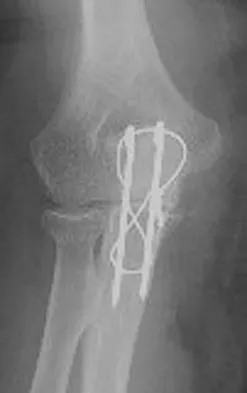

Figures 34a through 34c show the radiographs of a 51-year-old woman who injured her elbow in a fall from standing height. Examination reveals that elbow range of motion is limited by pain only. Management should consist of

Explanation

The radiographs show a small minimally displaced radial head fracture that is amenable to nonsurgical management. Early range-of-motion exercises will best restore function and minimize stiffness. A long arm cast for any length of time will result in severe elbow stiffness. Morrey BF: Radial head fracture, in Morrey BF (ed): The Elbow and Its Disorders, ed 3. Philadelphia, PA, WB Saunders, 2000, pp 341-364.